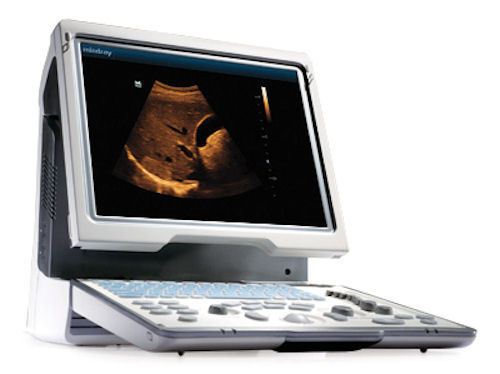

MindRay Diagnostic Ultrasound System DC7

Sale price$ 39,487.99

Save $ 700.00